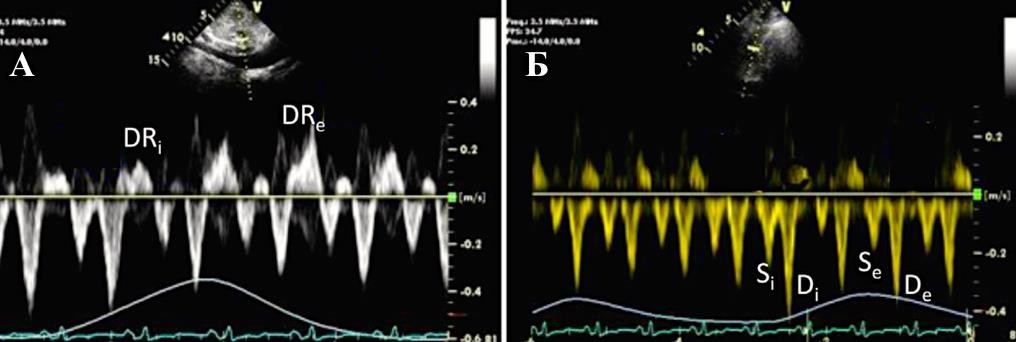

При констриктивном перикардите имеется значительная зависимость профиля кровотока через митральный и трикуспидальный клапаны от фаз дыхания:

-

по данным импульсно-волновой допплерографии, в начале вдоха максимальная скорость трансмитрального пика E уменьшается на ≥25%;

в начале выдоха максимальная скорость транстрикуспидального пика E уменьшается на ≥40% (Приложение А3, рис. 2) [116].

В диагностике констриктивного перикардита также может быть полезна тканевая допплерография, демонстрирующая так называемый феномен “annulus reversus”, заключающийся в том, что нормальная или повышенная ранняя диастолическая скорость движения медиальной части митрального кольца (медиальная е') оказывается выше, чем ранняя диастолическая скорость движения латеральной части фиброзного кольца (латеральная е’) (Приложение А3, рис. 3) [117].

Сочетание разнонаправленного смещения МЖП в зависимости от фаз дыхания с увеличением ранней диастолической скорости движения медиальной части митрального кольца (медиальная е') ≥9 см/сек имеет самую высокую диагностическую чувствительность (87%) и специфичность (91%) [118].